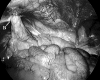

Figure 6.

Spigelian defect after reduction of contents. (A) Inferior epigastric vessels, (B) defect visualized above the inferior epigastric vessels, (C) Sigmoid colon.